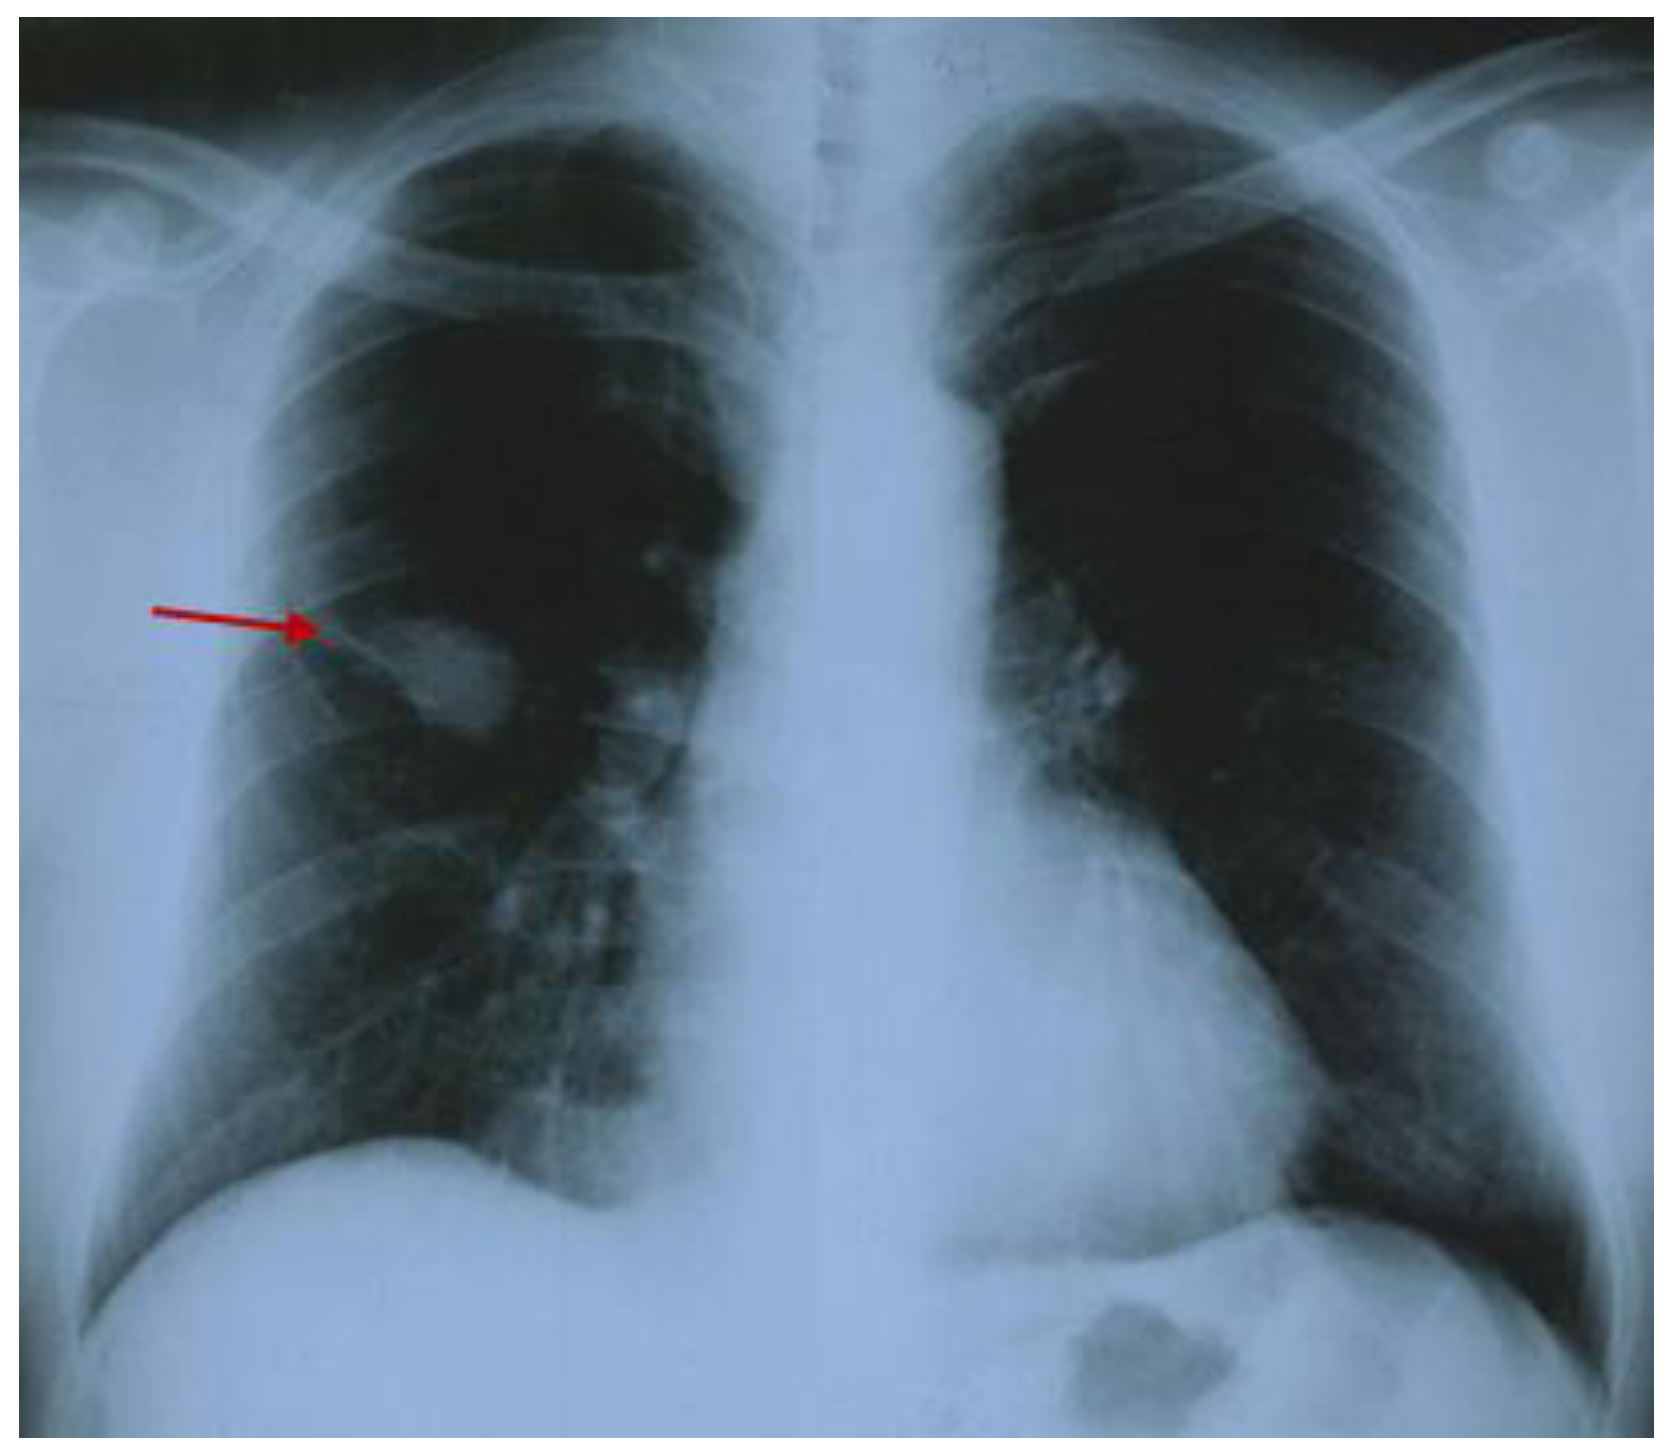

3.2.1. A Fine Index of Clinical Suspicion: Low Back Pain